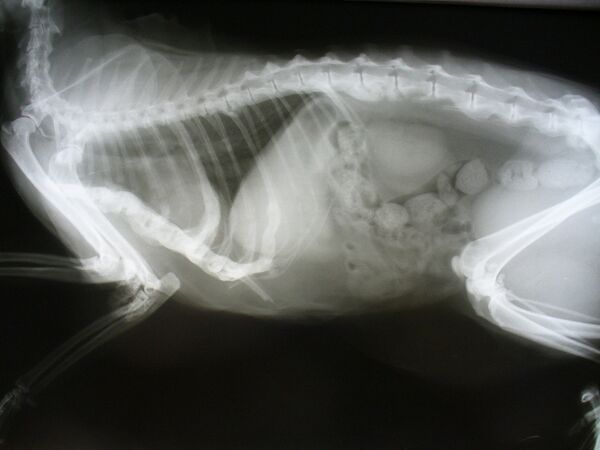

Диагноз ставит ветеринарный врач на основании данных осмотра и обследования. Обязательно проводится ультразвуковое и рентгенологическое исследование, чтобы исключить опухоли, воспалительные отеки, асцит и т. д.